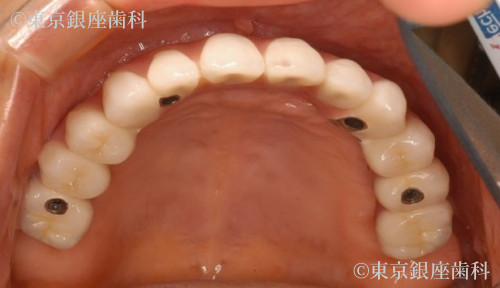

ワンデイインプラントによって全顎的な咬み合わせの再構築と審美の回復が得られることができた症例です。術前は奥歯での咬み合わせの安定が得られなかったため、口腔周囲筋肉の衰えが求められ、表情に張りが認められませんでした。術後は、咬み合わせの安定による、口腔周囲の筋肉の活性化のより表情にはりが戻りました。人口の歯による審美の回復と咬み合わせの安定による、表情筋の活発化と全顎的な口腔機能の回復が得られた症例です。